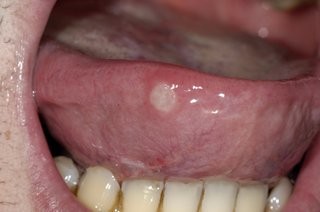

Canker Sores

These mouth ulcers are painful and unpleasant, but they are nothing to worry about. This common problem goes away on its own in around a week, and during this time they aren’t contagious. Research does point to stress being a cause, if you find yourself getting them regularly.

Oral Cancer

Often starting as a white patch, growth, or ulcer on the tongue that grows steadily, oral cancer is a serious condition that is most often seen in people who smoke or drink alcohol in larger quantities.